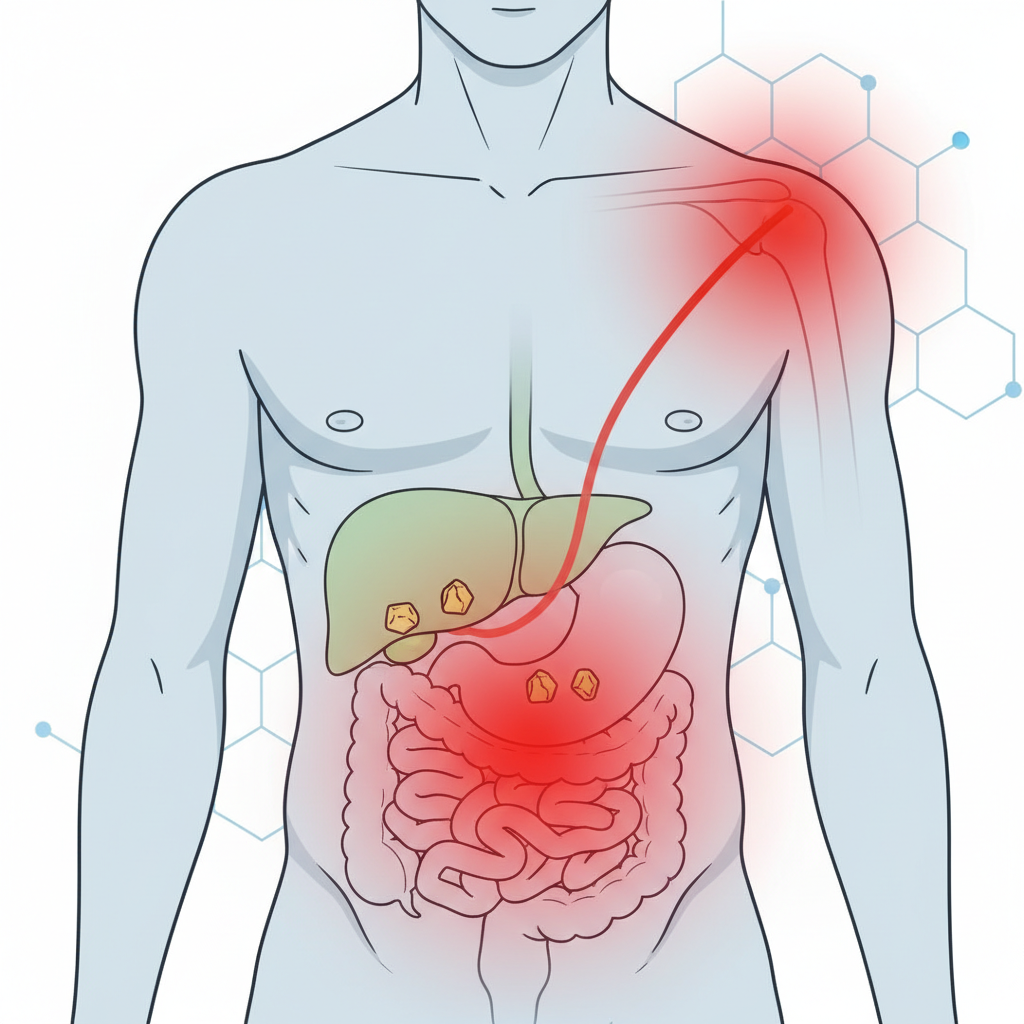

Safra taşı belirtileri kişiden kişiye değişebilir. Bazı hastalarda sadece hazımsızlık ve şişkinlik gibi hafif yakınmalar olurken, bazılarında aniden başlayan şiddetli ağrı atakları görülebilir. En tipik belirti, özellikle yağlı ve ağır bir yemekten sonra ortaya çıkan ağrıdır.

Safra koliği genellikle 30 dakika ile birkaç saat arasında sürebilir. Ağrı giderek artar, sonra yavaş yavaş azalabilir. Ancak ağrı 6 saatten uzun sürüyor, giderek şiddetleniyor veya ateş eşlik ediyorsa bu durum safra kesesi iltihabı (kolesistit) gibi daha ciddi bir tabloya işaret edebilir.

Evet. Hazımsızlık, mide yanması, şişkinlik gibi yakınmalar reflü ve gastritte de görülebilir. Ancak safra taşında daha tipik olan; sağ üst kadran ağrısı, yağlı yemekle tetiklenme ve sırta/sağ omuza vuran ağrıdır. Yine de net ayrım için değerlendirme ve görüntüleme gerekir.